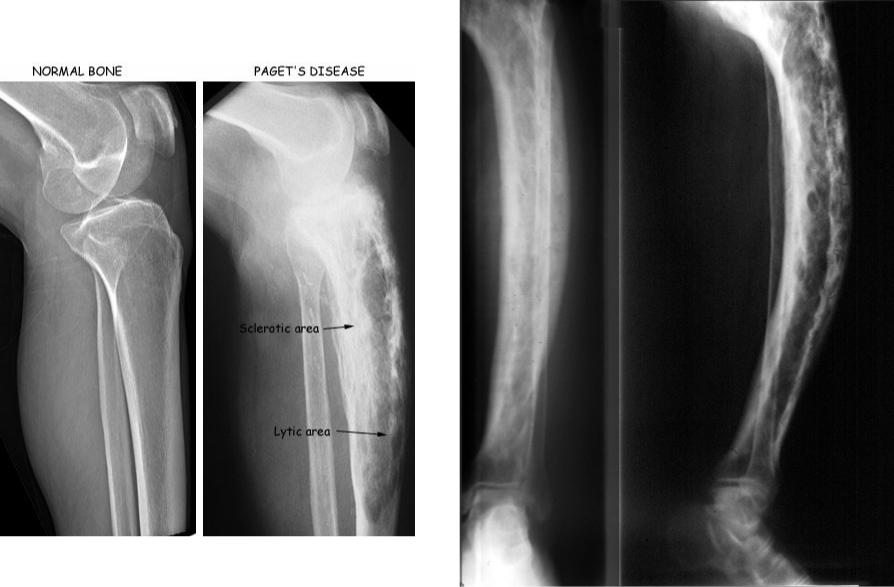

Рентгеновские снимки и визуализация болезни Педжета

Раздел: Мудрость в объективе